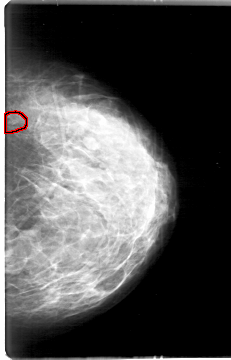

D_4171_1.LEFT_CC

LEFT_CC LINES 5386 PIXELS_PER_LINE 3451 BITS_PER_PIXEL 12 RESOLUTION 43.5 OVERLAY

FILE: D_4171_1.LEFT_CC.OVERLAY

TOTAL_ABNORMALITIES 1

ABNORMALITY 1

LESION_TYPE CALCIFICATION TYPE ROUND_AND_REGULAR-PLEOMORPHIC DISTRIBUTION CLUSTERED

ASSESSMENT 0

SUBTLETY 3

PATHOLOGY BENIGN

TOTAL_OUTLINES 1

BOUNDARY